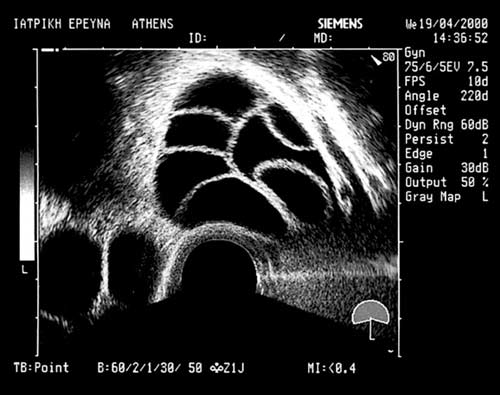

- Την ανάπτυξη των ωοθυλακίων και το αυξανόμενο πάχος του ενδομητρίου (με διακολπικά υπερηχογραφήματα).

Φυσιολογικά, υπάρχει συσχέτιση του αριθμού και του μεγέθους των ωοθυλακίων με την παραγόμενη οιστραδιόλη και επομένως με το πάχος του ενδομητρίου. Η ηχογένεια επίσης του ενδομητρίου έχει μεγάλη σημασία και ελέγχεται η «τριπλή διαστρωμάτωσή» του στη διάρκεια της διέγερσης. Η υπερηχογραφική εκτίμηση και οι ορμονικοί προσδιορισμοί γίνονται συνήθως σε συγκεκριμένες ημέρες διέγερσης.